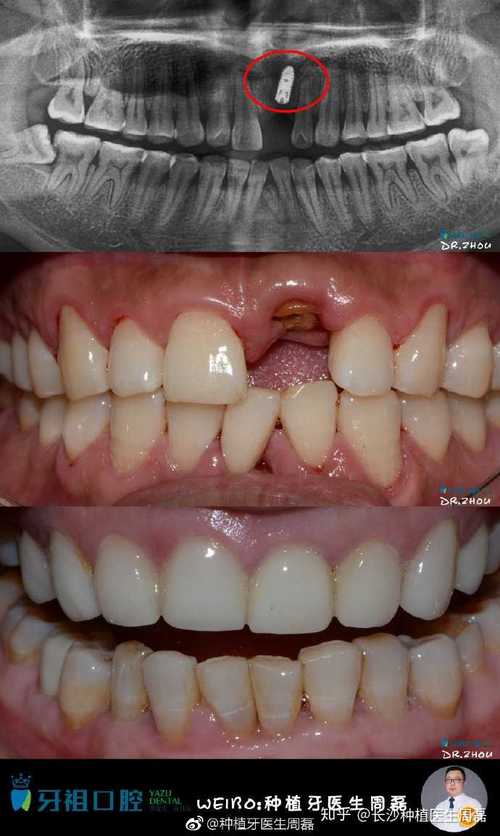

为了解决牙龈萎缩带来的问题,种植牙成为了一种常见的治疗方法。种植牙是将人工牙根植入牙槽骨中,然后再安装上牙冠,以取代缺失的牙齿。它不仅能够解决牙龈萎缩带来的影响,还能够恢复咀嚼功能和美观。

根据临床经验和研究数据,通常情况下,良好的种植牙可以使用十年甚至更长时间。这并不意味着所有的种植牙都能够达到这个寿命。一些患者可能由于种植牙周围的炎症或感染等问题,导致种植牙的寿命缩短。保持良好的口腔卫生和定期检查是至关重要的。

除了种植牙的质量和材料,患者的整体健康状况也会对种植牙的使用寿命产生影响。一些慢性疾病,如糖尿病、心脏病等,会增加种植牙的失败风险。在进行种植牙手术前,医生会对患者进行全面的身体检查,以确保患者的身体状况适合进行手术。